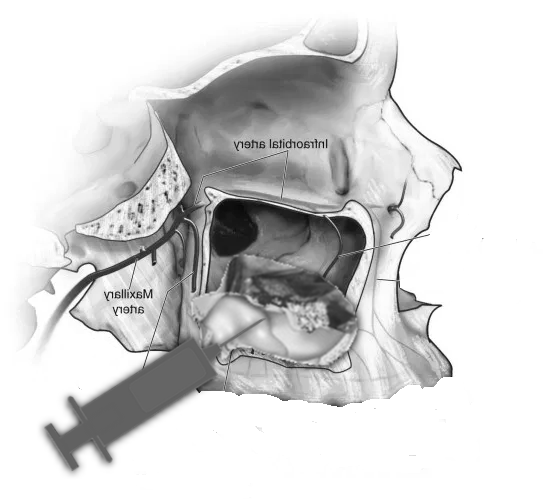

- Sinus Lift (Maxillary Sinus Elevation):

- At our center, we avoid this procedure thanks to Galileus Cerclage Sinus® surgery. In cases where the bone in the upper jaw is insufficient, a sinus lift procedure can be performed. This involves lifting the sinus membrane and adding bone graft material beneath it to improve bone density in the posterior maxilla.

- Avoiding Autologous Bone Grafts:

- Advanced techniques, like Galileus Cerclage Sinus®, aim to avoid autologous bone grafts, reducing the need to harvest bone from other parts of the body.